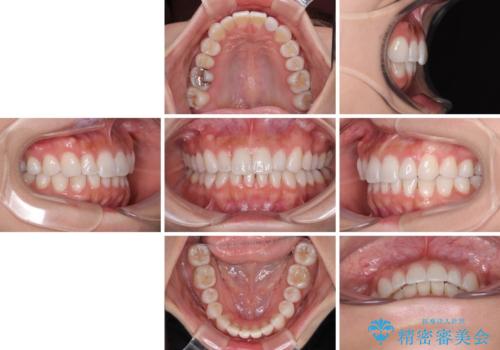

【モニター】前歯のデコボコと小さい前歯 インビザライン矯正とオールセラミッククラウン補綴治療

上下前歯の歯列不正はインビザラインにより整え、その後に、矮小歯の前歯をオーダーメイドタイプのオールセラミッククラウンにて補綴治療することとしました。

セラミッククラウンにて大きさを変更することを前提に矯正治療を開始したため、大変満足のいく仕上がりとなりました。